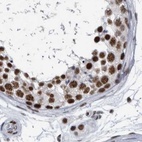

Immunohistochemical staining of human cerebral cortex, colon, kidney and testis using Anti-SF3A1 antibody HPA030083 (A) shows similar protein distribution across tissues to independent antibody HPA000690 (B).